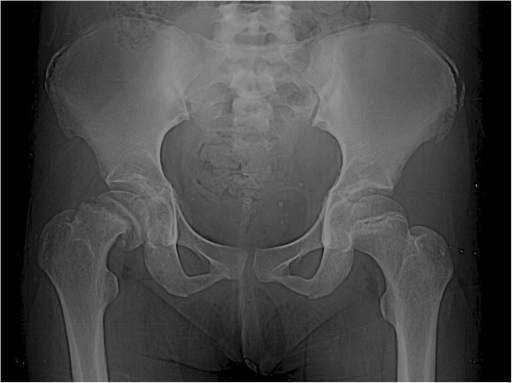

Puzzle 33

What's the Diagnosis?